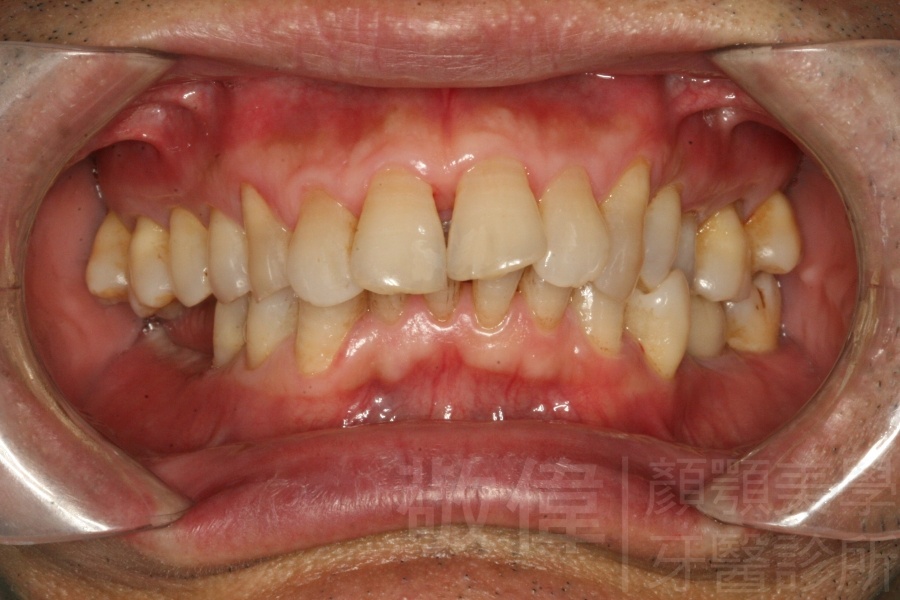

| 6 | 前牙美容 | 矯正+牙齦增補+晶鑽全瓷冠 | ||

| 7 | 前牙美容 | 矯正+晶鑽全瓷冠 | ||

| 8 | 前牙美容 | 快速矯正之美容晶瓷貼片及晶鑽瓷冠 | ||

| 9 | 前牙美容 | 矯正+美容晶瓷貼片 | ||

| 10 | 前牙美容 | 快速矯正之牙冠增長術+美容晶瓷貼片 |